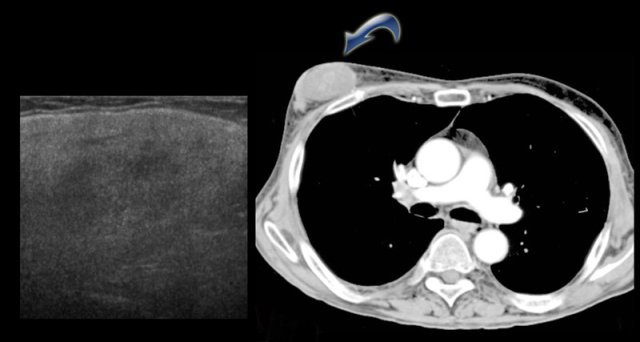

Liposarcoma Liposarcoma

Liposarcoma

A liposarcoma is a rare sarcoma.

It presents as a slowly enlarging painful mass.

It is usually of water-density and is not typically fatty.

On the CT on the left you can see the density of the lesion that proved to be a liposarcoma.